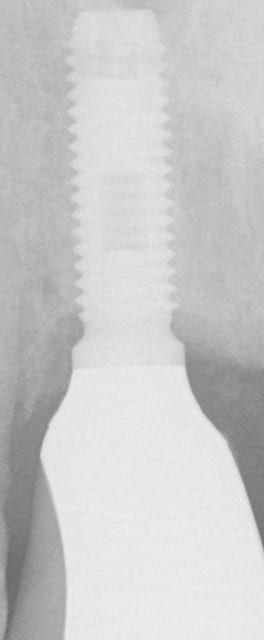

Auriez vous une idée sur le type d'implant?

La vis prothétique s'est fracturée...

Nobel MK3...;-)

la vis est vraisemblablement en or...pas forcément le plus simple à retirer car l'or se matte sur le filetage en titane...